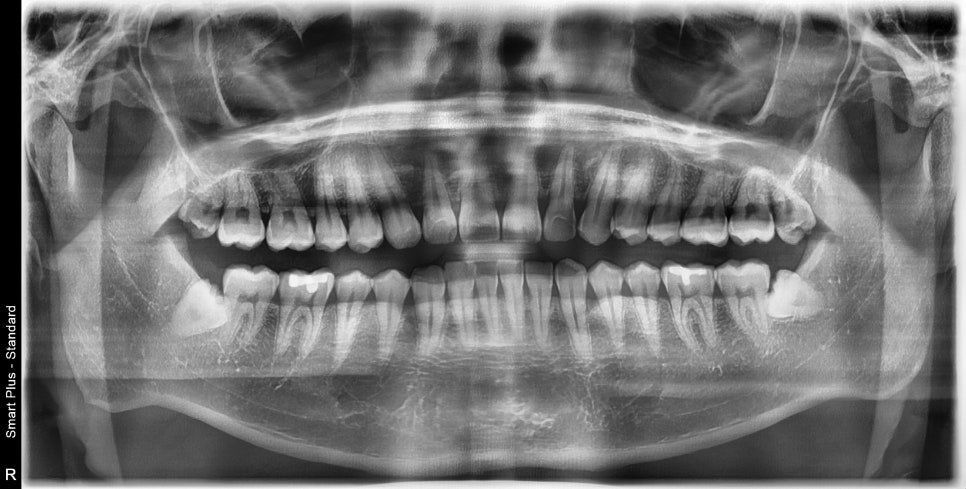

치과에 오시면 엑스레이를 찍게 되시는데요.

엑스레이에는 육안으로 볼 수 없는 치아의 상태나

매복 사랑니의 유무 등을 쉽게 알 수 있습니다.

위 환자분은 4개의 사랑니가 있고,

아래 2개의 사랑니는 완전 매복이시지만

왼쪽의 사랑니는 치아의 머리가 살짝 나와 있었습니다.

오랜만에 정기점검을 오셔서 체크 겸 엑스레이를 찍어보았습니다.

발치 주변이 깔끔하게 치유가 된 것을 볼 수 있습니다.